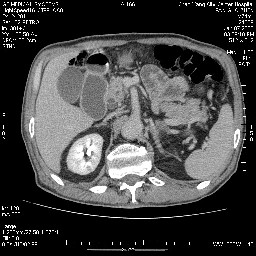

女,74岁,呕吐10余日

壶腹部的占位性病变,考虑为十二指肠癌并梗阻,但脾内多发性低密度区为转移吗?

还有胃、脾之间可见有侧支循环建立。左肾盂积水。

十二指肠水平段腔内占位伴梗阻,中等度较为均匀的强化,洗脱慢,区域淋巴结显示增多,符合腺癌表现。下腔静脉变异。

十二指肠降段扩张,水平段狭窄成鼠尾状,肠壁明显增厚,胰腺勾突增大成不均匀强化,其内可见低密度区,胆囊增大,1十二指肠水平段腺癌侵犯胰腺勾突可能大,2胰腺癌侵犯十二指肠(只有胆囊增大没有肝内外胆管扩张不好解释)代除外.

十二指肠降段扩张,水平段狭窄成鼠尾状,肠壁明显增厚,胰腺勾突增大成不均匀强化,其内可见低密度区,胆囊增大,1十二指肠水平段腺癌侵犯胰腺勾突可能大,2胰腺癌侵犯十二指肠 。

今日手术结果:胰腺钩突癌侵犯十二直肠,腹腔淋巴结转移.